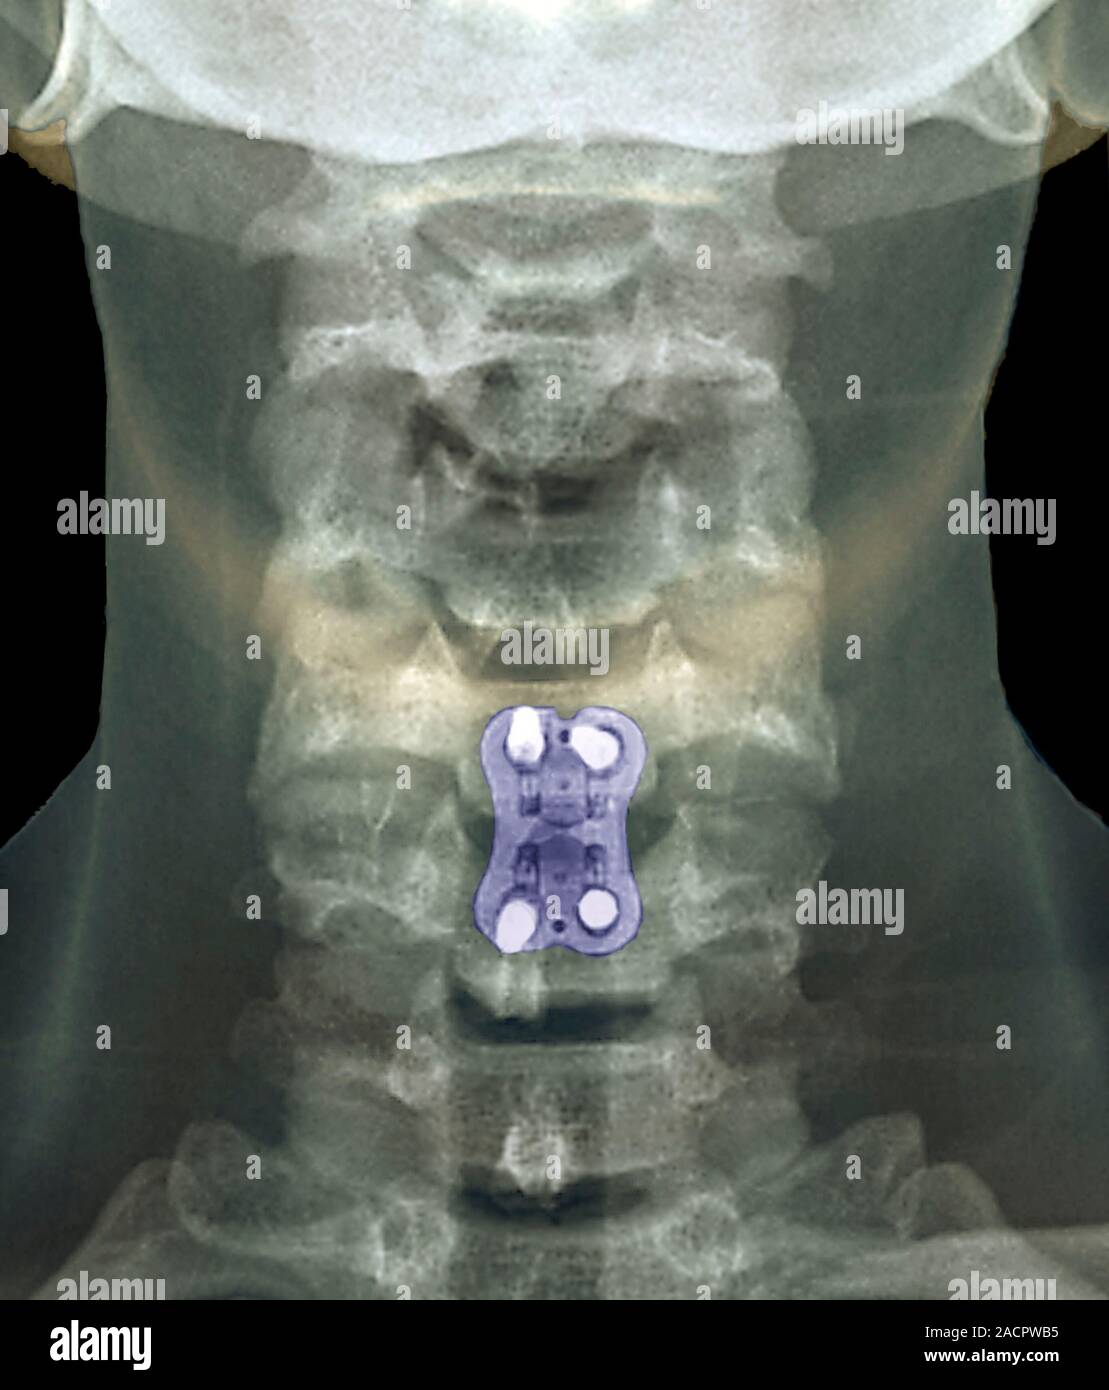

Osteoarthritis In My Neck. With less padding between them, vertebrae may rub against each other. cervical refers to seven stacked bones (vertebrae) in your neck. If this occurs, your symptoms may include numbness and weakness in the arms, hands, and fingers. grinding or popping noise or sensation when you turn your neck. Most of us will eventually develop osteoarthritis, and for some, it can be a real pain in the neck. Cervical spondylosis is also called cervical osteoarthritis. osteoarthritis in the neck. learn about the signs and symptoms of arthritis in the neck, as well as treatment options. Spondylosis is when parts of your spine begin to wear out. It is a condition involving changes to the bones, disks, and joints of the neck,. stretching and strengthening exercises can help keep your neck limber and relieve arthritis pain. neck arthritis, also called cervical spondylosis, is a common condition that occurs when the cartilage and bones in the neck gradually wear down over time, leading to joint inflammation,. Osteoarthritis in the neck is the degeneration of joints, vertebrae, and discs in the cervical portion of the spine. In some cases, cervical spondylosis results in a narrowing of the space needed for the spinal cord or nerve roots. 11 min read.